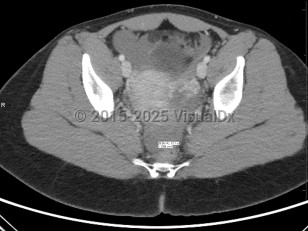

The term ectopic pregnancy refers to implantation of a developing blastocyst at any location outside of the endometrial cavity. Ectopic pregnancies can be found in the cervix, cornua, fallopian tubes, ovaries, or a prior cesarean delivery scar, or, more rarely, attached to the abdominal lining, bowel, or other viscera. The most common location is the fallopian tube, specifically the ampulla, which accounts for about 70%-80% of cases, followed by the isthmus and fimbria. Prevalence is estimated at 25 in 1000 pregnancies, with fewer than 200 000 cases in the United States per year. It is a medical emergency.

Presentation can vary. Patients may present with a positive home pregnancy test and unilateral lower quadrant pain that is often sharp / stabbing in nature. Some will present after tubal rupture and be hemodynamically unstable. Others may present with only vaginal spotting and be unaware they are even pregnant. Therefore, one must have a high index of suspicion when a patient arrives with a positive pregnancy test and symptomatology. As many as 18% of women presenting to the emergency department with first-trimester bleeding, pain, or both will be found to have an ectopic pregnancy.

A 2011 consensus statement provides definitions that draw attention to the complexity of evaluating for and diagnosing ectopic pregnancy, with 5 categories based on sonographic findings:

- Definitive intrauterine pregnancy

- Probable intrauterine pregnancy

- Pregnancy of unknown location

- Probable ectopic pregnancy

- Definite ectopic pregnancy